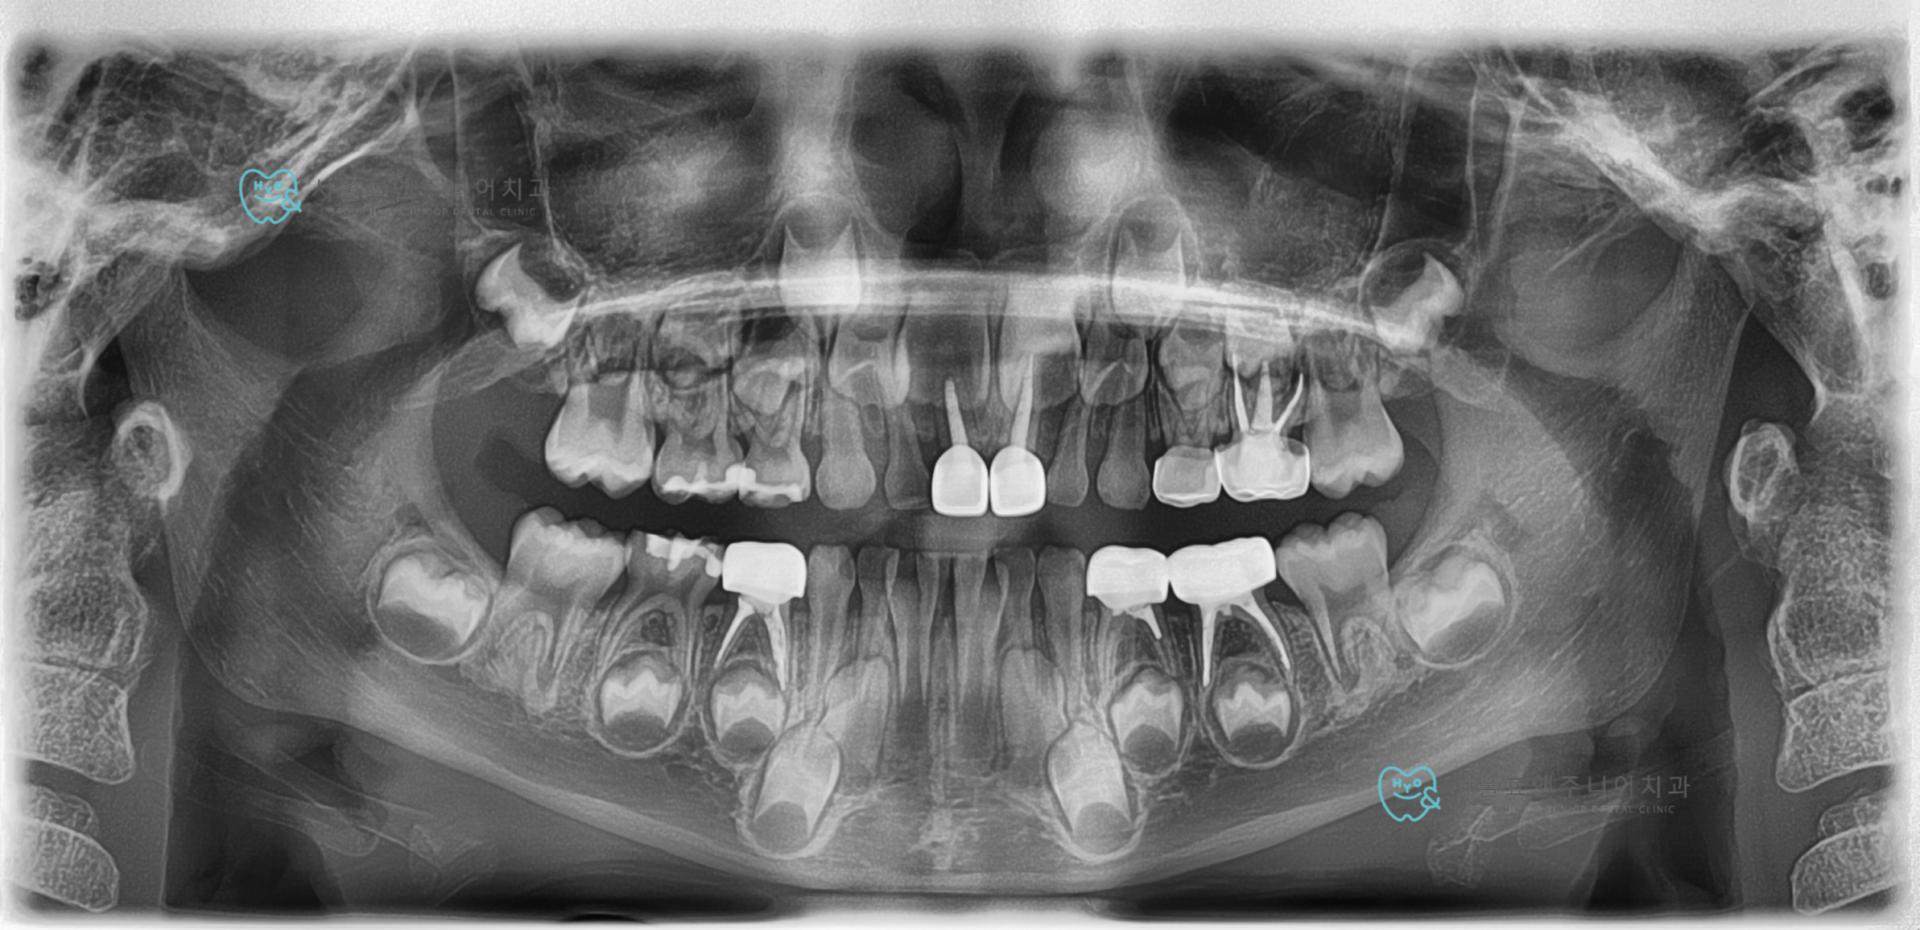

전체적인 충치치료 2년3개월 후 정기검진사진. 신경치료한 부위가 모두 염증없고 레진치료한 부위 이차충치 없이 잘 유지되고 있습니다.

2년 3개월 전 아이가 아주 어렸을 때 심한 충치로 한번에 수면치료로 어금니와 앞니 충치를 치료했었는데요, 그때 아래쪽 잘 보이는 어금니는 지르코니아 크라운을 했고 상대적으로 잘 안보이는 위쪽 어금니는 은니, 즉 SS 크라운을 했습니다.